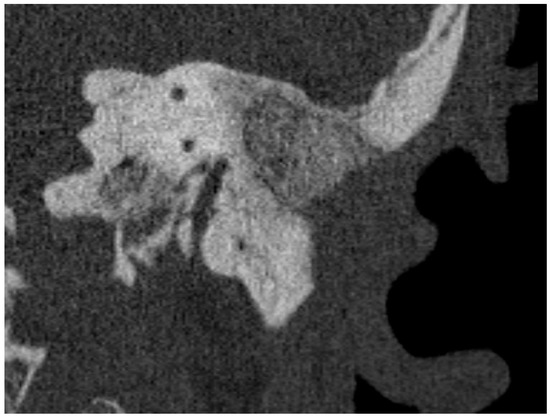

A Bone-Thickness Map as a Guide for Bone-Anchored Port Implantation Surgery in the Temporal Bone

The bone-anchored port (BAP) is an investigational implant, which is intended to be fixed on the temporal bone and provide vascular access. There are a number of implants taking advantage of the stability and available room in the temporal bone. These devices range from implantable hearing aids to percutaneous ports. During temporal bone surgery, injuring critical anatomical structures must be avoided. Several methods for computer-assisted temporal bone surgery are reported, which typically add an additional procedure for the patient. We propose a surgical guide in the form of a bone-thickness map displaying anatomical landmarks that can be used for planning of the surgery, and for the intra-operative decision of the implant’s location. The retro-auricular region of the temporal and parietal bone was marked on cone-beam computed tomography scans and tridimensional surfaces displaying the bone thickness were created from this space. We compared this method using a thickness map (n = 10) with conventional surgery without assistance (n = 5) in isolated human anatomical whole head specimens. The use of the thickness map reduced the rate of Dura Mater exposition from 100% to 20% and suppressed sigmoid sinus exposures. The study shows that a bone-thickness map can be used as a low-complexity method to improve patient’s safety during BAP surgery in the temporal bone. Full article